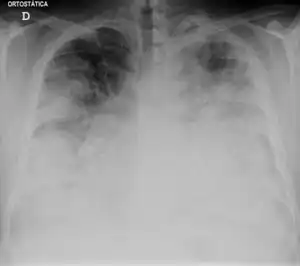

| Chest X-ray of a severe case of legionellosis upon admission to the emergency department. | |